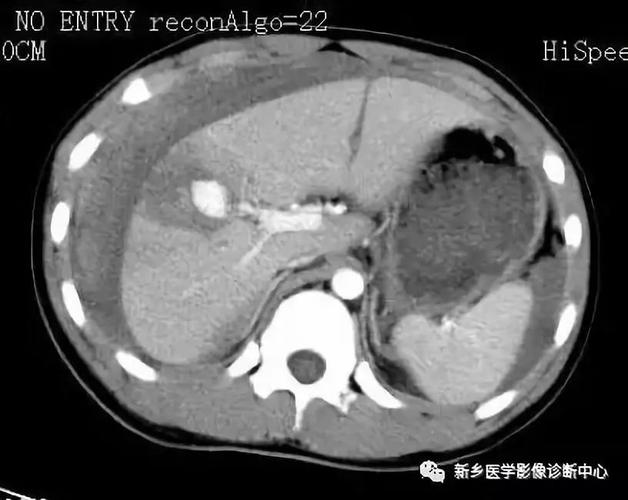

五,肝破裂出血

ct诊断:高度怀疑肝左内叶肝破裂. 手术

肝破裂

肝破裂ct影像表现

肝脏破裂ct图片

肝脏破裂出血ct图片